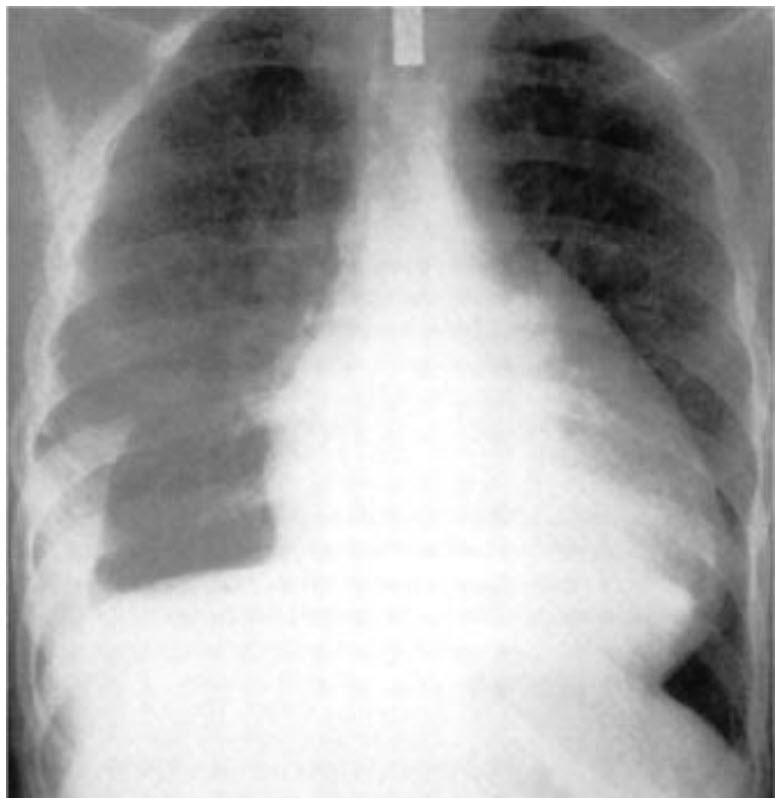

A 35-year-old woman was recently diagnosed with systemic lupus erythematosus. She presents with progressive dyspnea and chest pain for 2 weeks. Jugular venous distension is present and heart sounds are muffled. ECG shows electrical alternans. Chest x-ray is shown.

This patient has the typical water bottle heart seen on the chest x-ray of patients with pericardial effusion, which may occur in patients with lupus. Patients with pericardial effusion may develop cardiac tamponade, a condition in which pericar-dial fluid impedes diastolic filling, resulting in reduced cardiac output and hypotension. In these patients, the ECG may show pulsus alternans. Typical physical examination findings in cardiac tamponade include elevation of jugular venous pressure and pulsus paradoxus (paradoxical pulse). Pulsus paradoxus is defined as more than 10-mm Hg decline in systolic arterial pressure during inspiration. Normally during inspiration the intrathoracic pressure becomes more negative, hence facilitating increased venous return and increased blood flow to right ventricle. This is accompanied by bulging of the interventricular septum into the left ventricular cavity, which impedes left ventricular filling slightly and causes a drop in systolic blood pressure. This is normally less than 10 mm Hg. In cardiac tamponade this phenomenon is exaggerated. In contrast to pulmonary edema, the lungs of patients with cardiac tamponade are usually clear. Instead of a strong apical beat, one would expect a weak apical pulse and absent or muffled heart sound due to the fluid accumulation in the pericardial sac. An S3 or third heart sound usually signifies systolic heart failure in adults. An S3 is not found in cardiac tamponade. Epigastric and right upper quadrant tenderness can be seen in either in acute right-sided heart failure or cardiac tamponade due to passive congestion of the liver, but this finding is not specific. Cardiac tamponade is often fatal and pericardiocentesis may be life saving.